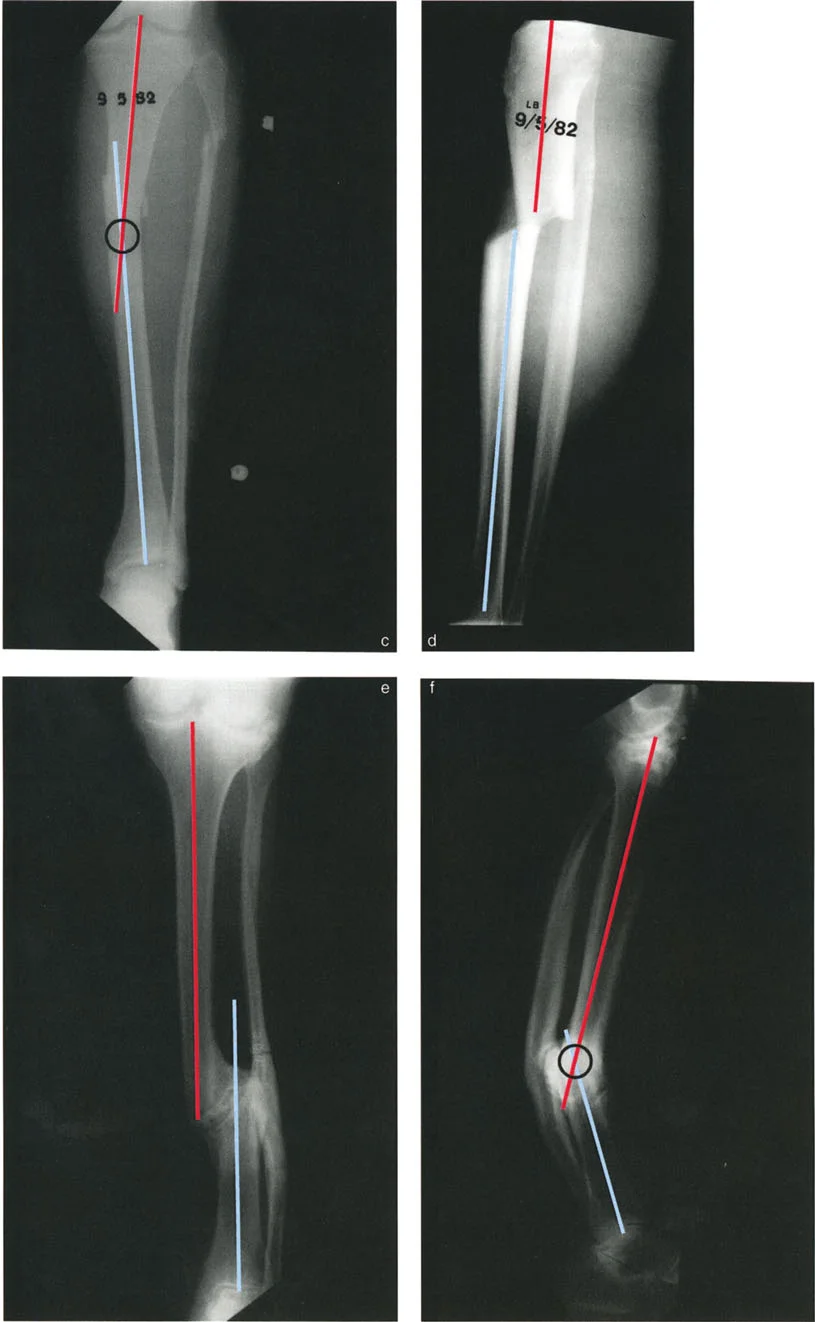

تشوهات المستوى التشريحي بزاوية 90 درجة

في هذا النوع، يكون الانحراف في مستوى تشريحي واحد (مثل المستوى الأمامي الخلفي)، بينما يكون الانزياح في المستوى التشريحي الآخر العمودي عليه (مثل المستوى الجانبي). لا يوجد انزياح في مستوى الانحراف، ولا يوجد انحراف في مستوى الانزياح. يكون مركز دوران الانحراف (CORA) عند مستوى الكسر.

مثال: التئام خاطئ في عظم الساق الأيسر حيث يوجد انحراف في المستوى الأمامي (الواجهة الأمامية) وانزياح في المستوى السهمي (الجانبي). لا يوجد انزياح في المستوى الأمامي ولا انحراف في المستوى السهمي.